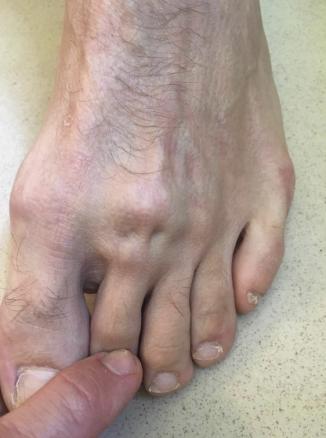

Après trois semaines de repos et la persistance de la douleur limitant la marche, un scanner est réalisé, qui montre une nécrose de la tête du 2e métatarsien (fig. 3).